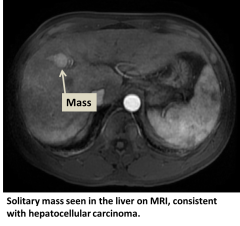

Hepatocellular carcinoma (HCC) is the most common type of primary liver cancer. Primary liver cancer refers to cancer that originates in the liver rather than cancers from other organs that metastasize to the liver (see metastatic liver cancer). HCC can start as a single tumor or as several tumor nodules across the liver.

- MRI